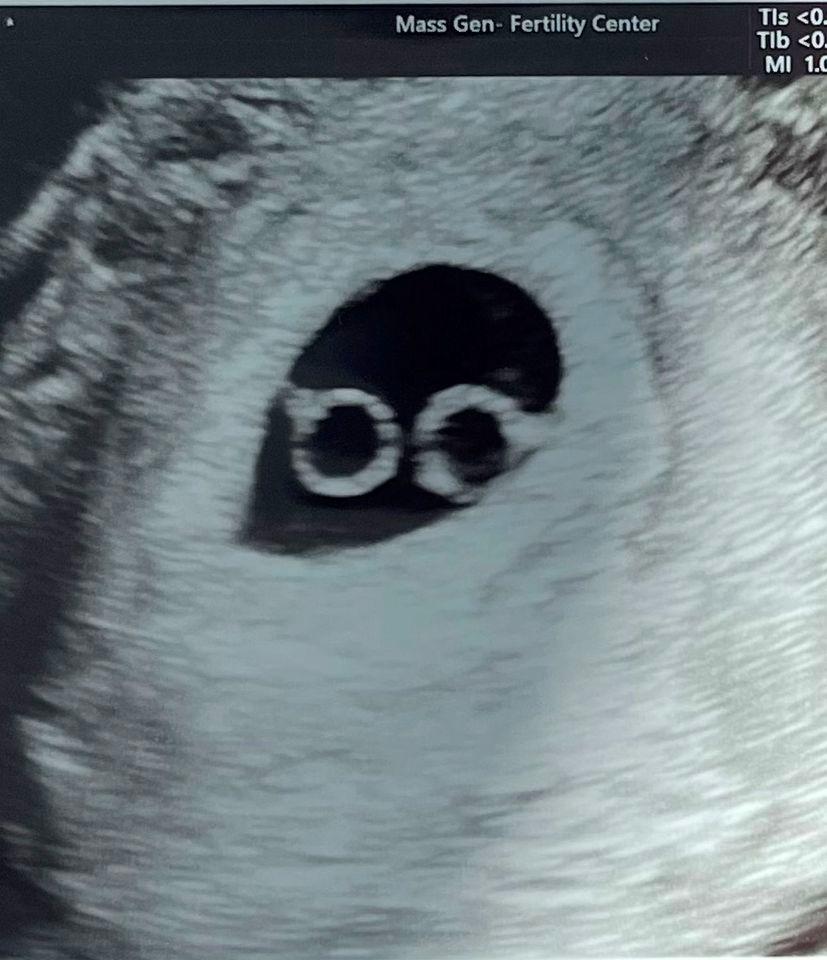

On June 24, 2024, on Chris’ birthday, the couple received a surprise regarding Abby’s pregnancy: she was carrying twins.

Abby was six weeks into her pregnancy when they had the first ultrasound. But what should’ve been joyous news for Abby, however, instead turned into a moment of dread when she thought about a warning she’d previously gotten involving pregnancy and her heart condition.

“I was absolutely terrified because I had been told, ‘If you have twins, it will likely kill you,’ ” Abby remembers.